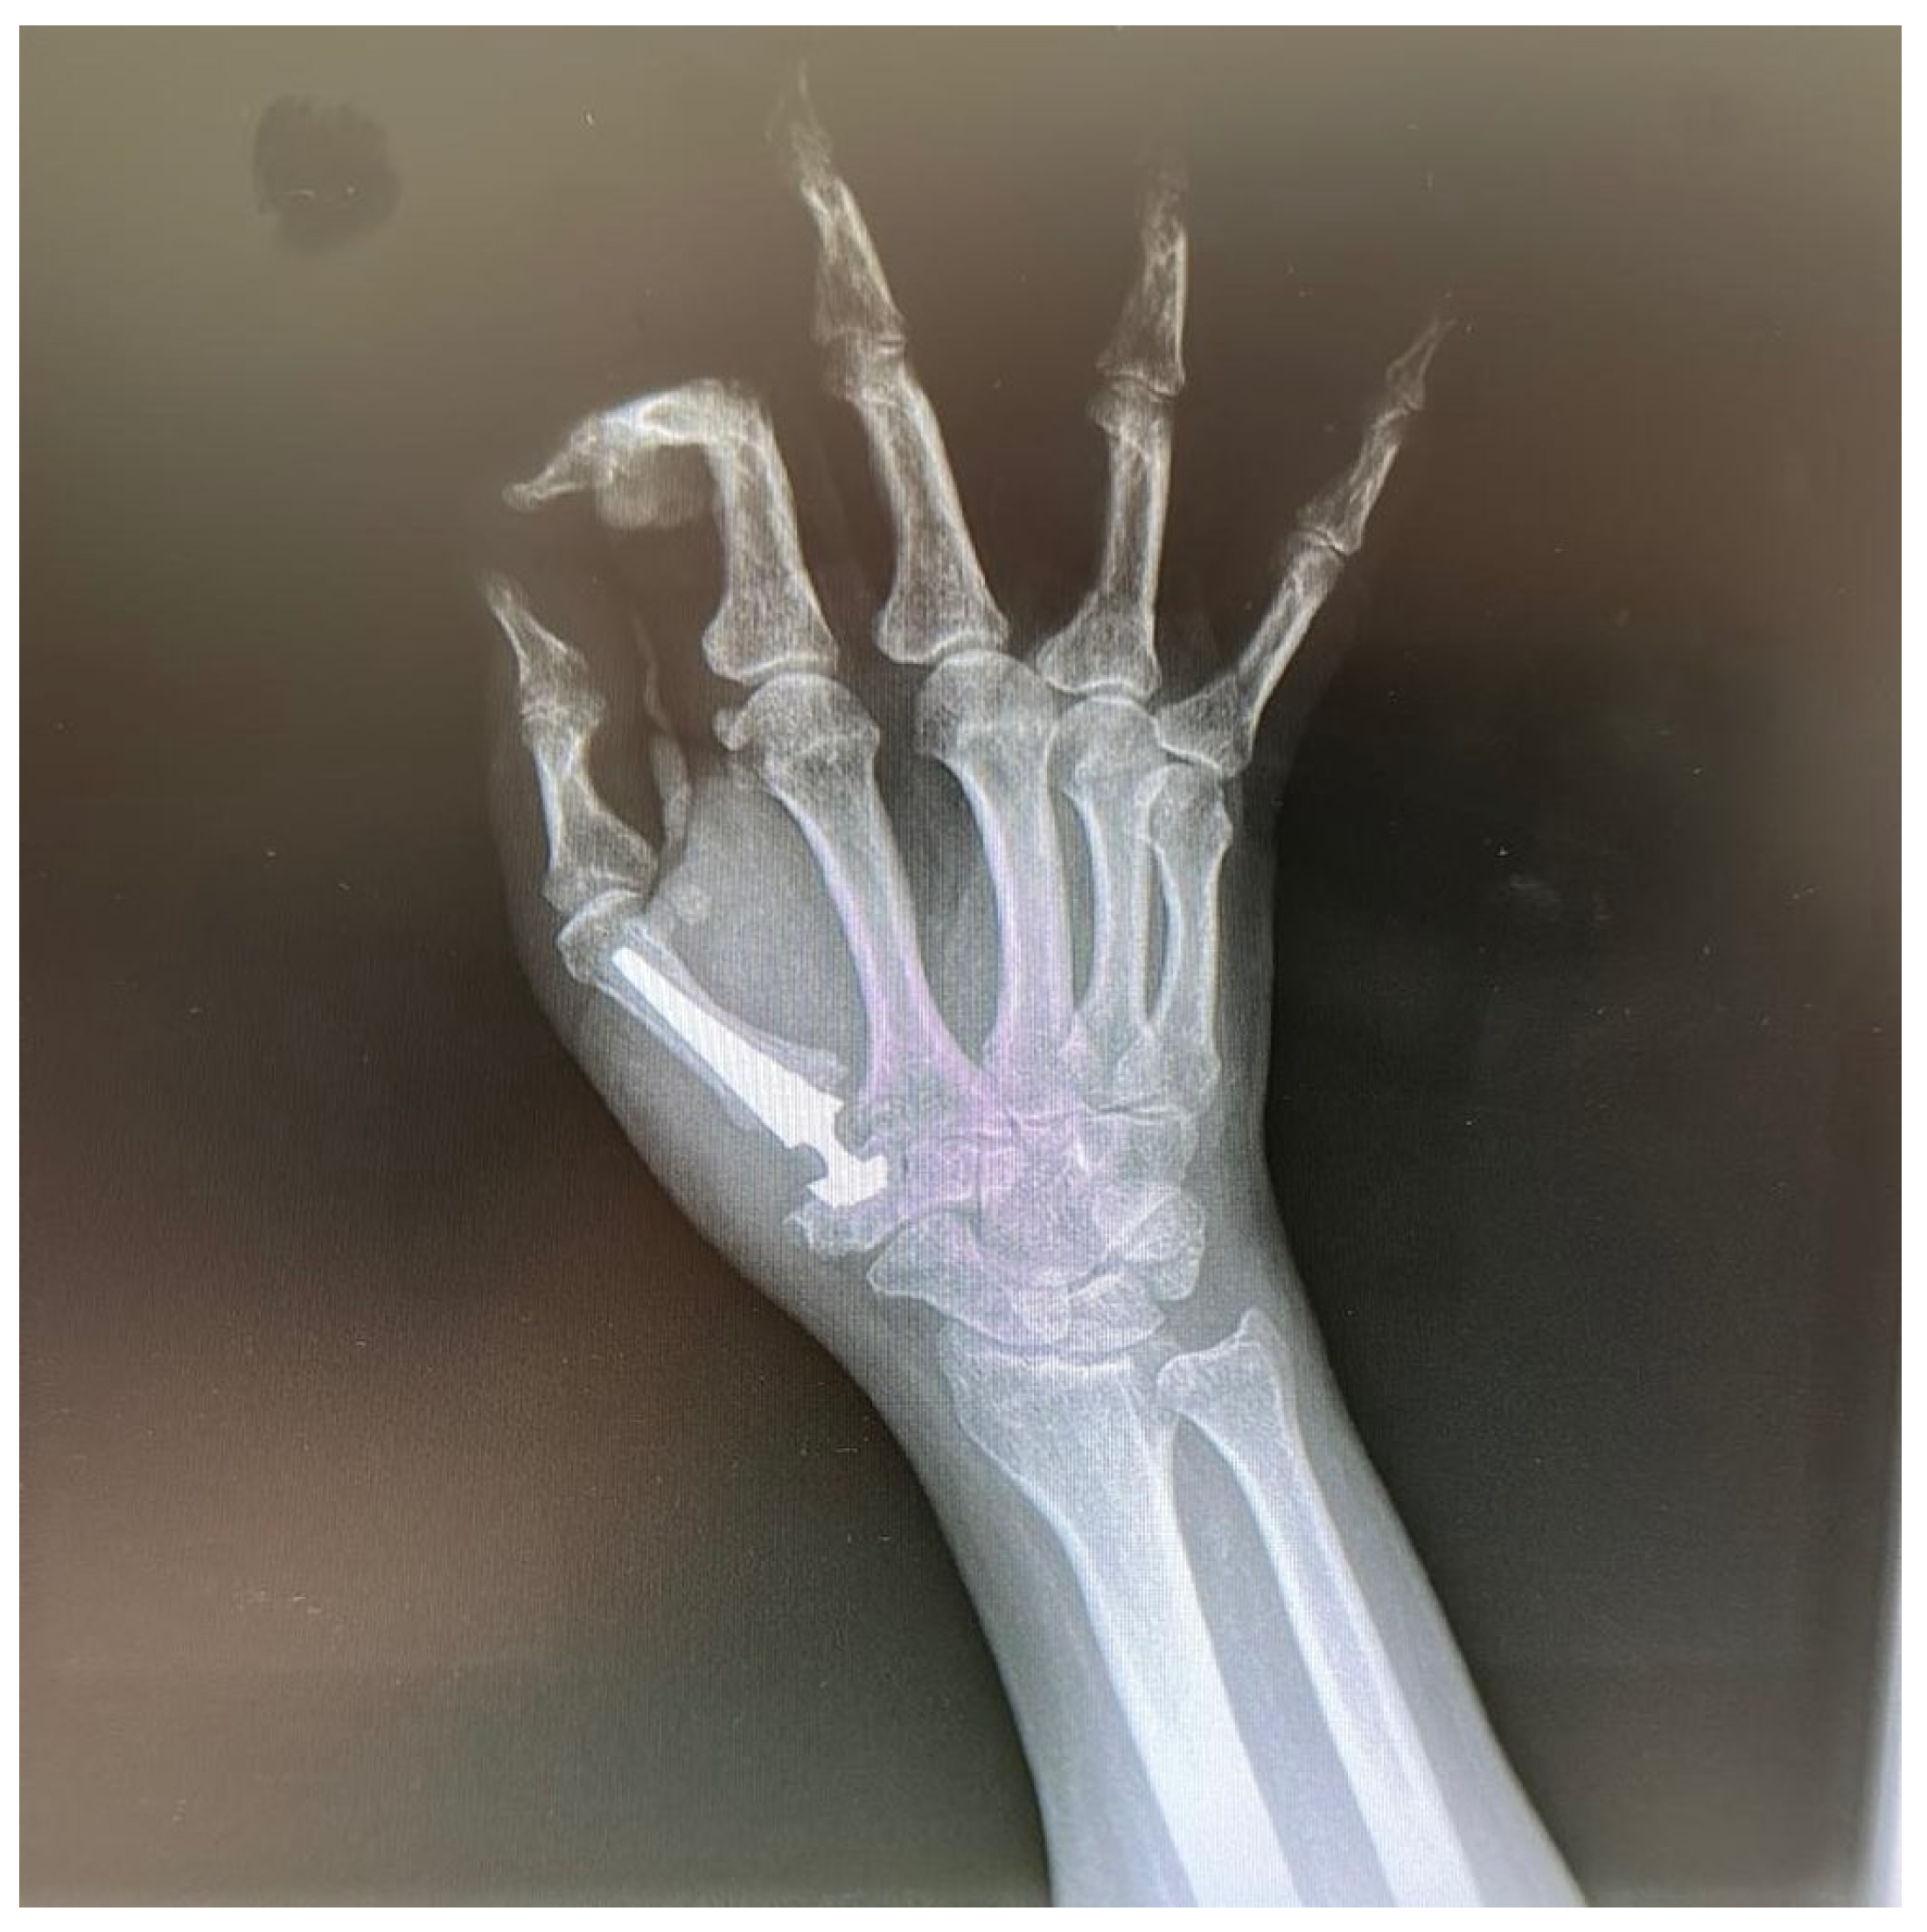

Primary Trapeziometacarpal (TMC) Arthroplasty for Bennett Fracture in Setting of Severe Thumb Osteoarthritis: A Case Report

2. Case Report